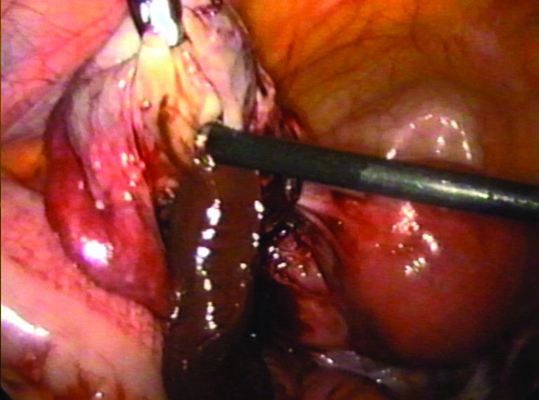

子宮頸糜爛圖片

宮頸糜爛 (8)

宮頸糜爛 (9)

宮頸糜爛 (56)

宮頸糜爛 (57)

宮頸糜爛 (58)

宮頸糜爛 (59)

宮頸糜爛 (6)

宮頸糜爛 (60)

宮頸糜爛 (7)